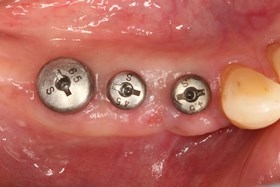

植牙後癒合狀況良好